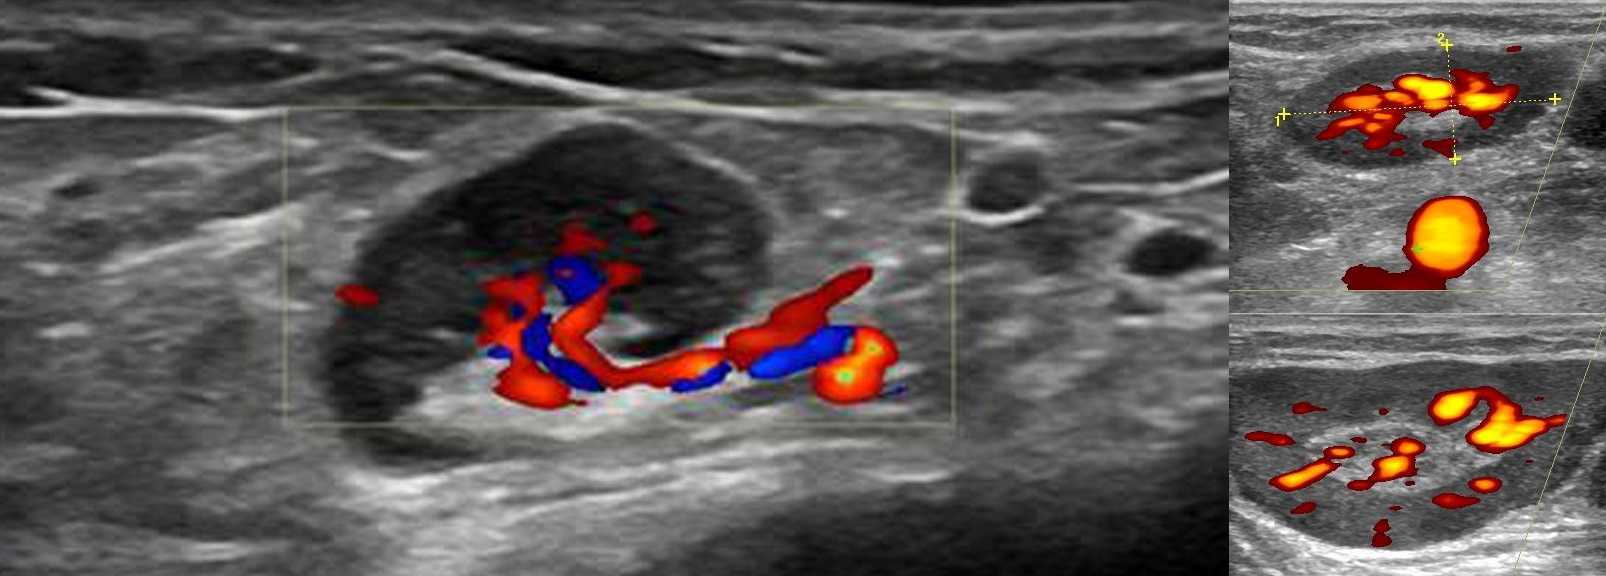

УЗИ лимфоузлов при лимфоме Ходжкина

Раздел: Образы вокруг